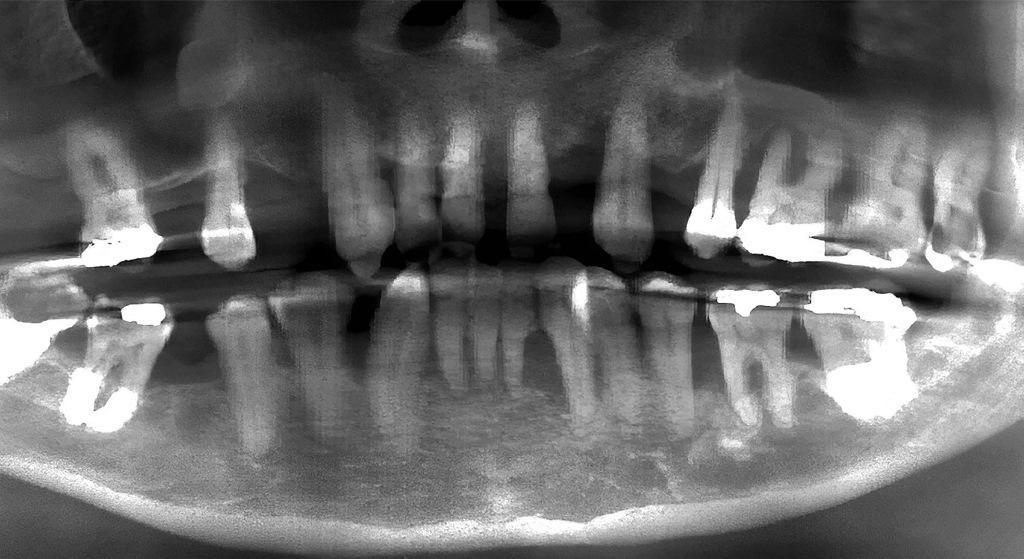

49-летний мужчина обратился с жалобами на разрушение зубов верхней и нижней челюсти. Результаты клинических и рентгенологических исследований показали тяжелое заболевание пародонта, общую потерю костной ткани, увеличение расстояния между передними зубами и подвижность зубов, а также общее неудовлетворительное соблюдение гигиены (фото 1a-b, 2a). Пациент был проинформирован о результатах исследования и было обсуждено несколько вариантов лечения, включая полные и/или частичные протезы, съемные протезы на имплантатах и несъемные протезы на имплантатах. После обсуждения вариантов пациент выбрал несъемные протезы на имплантатах для всей челюсти.

Фото 2a: Предоперационная панорамная рентгенограмма, показывающая обширную потерю костной ткани.